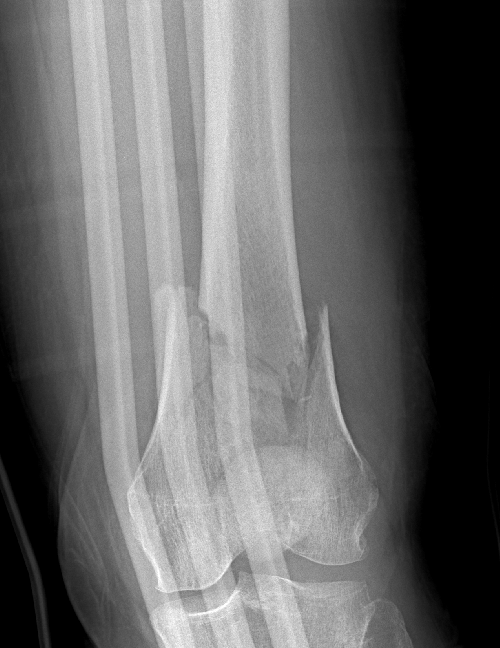

why did this go onto non union?

60yo F, moderate energy trauma. Methotrexate and Secukinumab. Index LISS OP 10m ago

Im expecting 1000's opinions, so have created a poll to capture the vibe⬇️